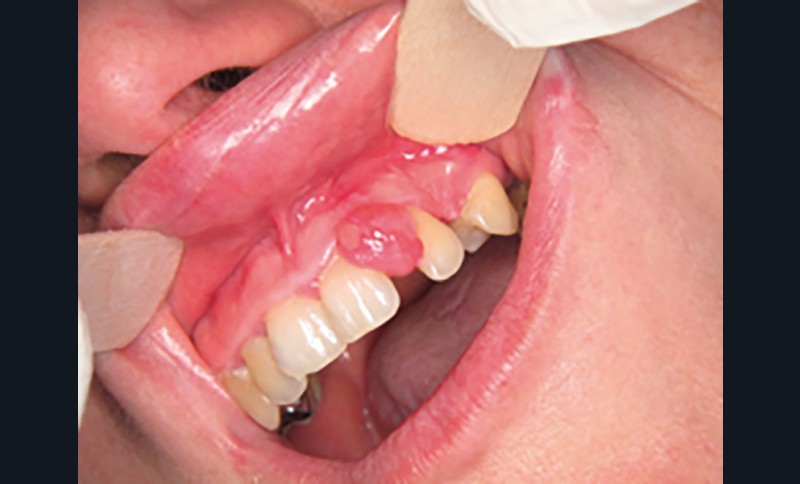

Motif de la consultation. Patiente de 25 ans venue consulter pour l’apparition d’une tuméfaction gingivale « disgracieuse » et non douloureuse.

Examen clinique. Il révélait une lésion nodulaire de 1 cm de grand axe, localisée entre 21 et 22 en malposition. Le nodule était érythémateux et ulcéré sur sa face vestibulaire. Il présentait un caractère sessile. Le sondage à hauteur de la 21 mettait en évidence une poche parodontale de 5 mm au niveau distal.

Synthèse. Le tableau clinique et l’examen anatomopathologique sont évocateurs d’une épulis fibroblastique ulcérée calcifiante et ossifiante. Cette forme se distingue des épulis inflammatoires et fibreuses par la présence d’une ulcération et d’une métaplasie calcifiante et osseuse. Le traitement repose sur l’exérèse et un suivi, car cette forme clinique est plus récidivante que les épulis fibreuses ou inflammatoires simples.